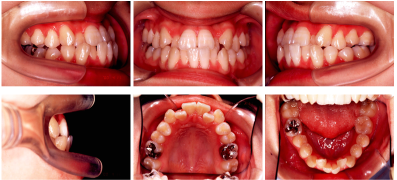

- 模型とその分析

_

- 口腔内写真と顔面写真